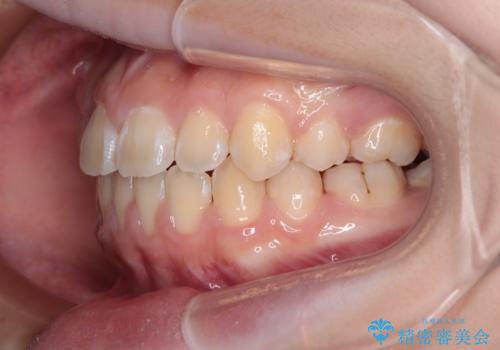

舌の突出癖により上下前歯は接触できず、更には前方に押し出されて出っ歯になっている状態でした。

上下左右の第一小臼歯4本を抜歯し、ワイヤー装置での抜歯矯正を行っていくのですが、原因である舌の突出癖を改善しないことには治療がうまく進められないため、舌のトレーニングを徹底するよう指導していくこととしました。